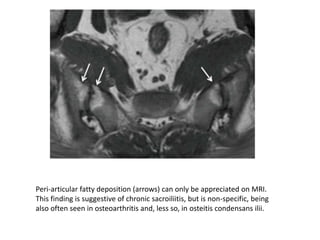

Peri-articular fatty deposition (arrows) can only be appreciated on MRI.

This finding is suggestive of chronic sacroiliitis, but is non-specific, being

also often seen in osteoarthritis and, less so, in osteitis condensans ilii.